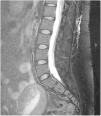

- -

RM espinal con Gd+ iv (mielo-RM): se recomienda que incluya una secuencia T2 de supresión grasa. Puede observar captación de contraste paquimeníngeo, vainas de las raíces nerviosas dilatadas, ingurgitación de senos venosos epidurales y divertículos meníngeos50,62. La mielo-RM no solo sirve para observar signos indirectos de HIE, sino que también puede localizar la fuga de LCR, objetivando colecciones de fluidos en los tejidos blandos epidurales (fig. 3, no compresivas habitualmente, en un 60% de casos59. Por ello, se recomienda solicitar siempre mielo-RM, simultánea a la RM craneal, ante la sospecha clínica de HIE59.